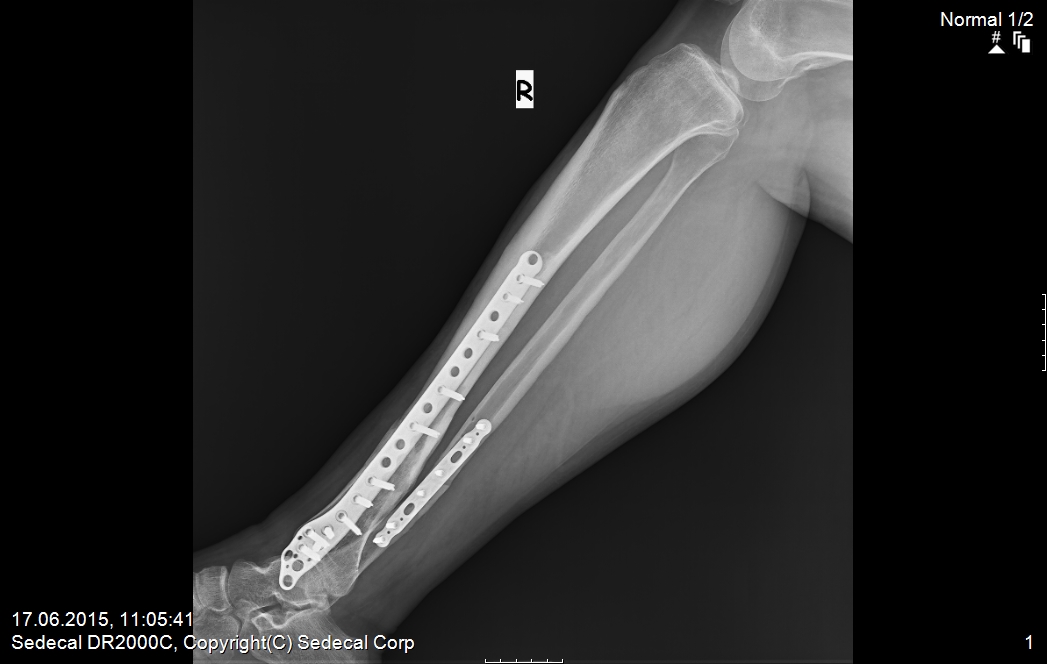

11 Şub Bacakta kaynamayan kırıkta (psödoartroz) tedavi – vaka 2 by admin in TRAVMA (KIRIK-ÇIKIK) VAKA ÖRNEKLERİComments ameliyat öncesi 1 ameliyat öncesi 2 ameliyat sonrası 1 ameliyat sonrası2